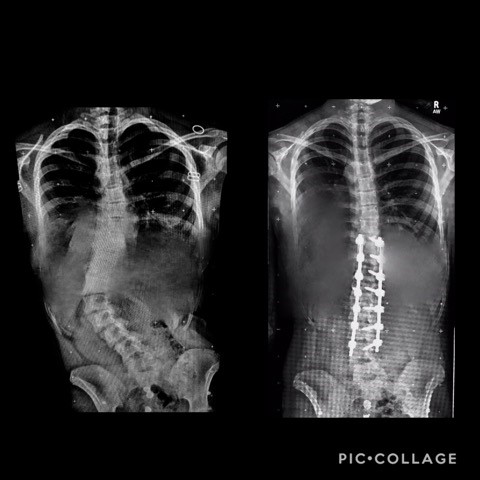

Hey there! My name is Rose, and this is a summary of my scoliosis story! In the summer of 2018 at the age of 12, I was diagnosed with type 4 Adolescent Idiopathic Scoliosis after seeing a Pediatrician and an Orthopedic Surgeon who specialized in spinal deformities. After I was diagnosed, I had to wear an overnight brace. I wore it for about 6 months to try to help my 30-40-degree curvature in my spine. After months of it including an MRI, I stopped wearing it because it made no change. In winter of 2019 I was told that I might need surgery by my orthopedic surgeon. My parents and I chose to get a 2nd opinion from another surgeon. Come to find out, everything checked out the same. I continued seeing my original orthopedic surgeon.

In the summer of 2019, my scoliosis had almost jumped 3/4 into higher numbers, this was not good news! Every time I would go to my regular checkups, they would do an X-ray and, sometimes it would not be very much different and, sometimes it would! In December of 2019, my spine had developed a 59-degree curve but within months it went up to 64 degrees.

On June 4th of 2020 I had partial spinal fusion surgery to correct my 64-degree curve that had only continued to increase. As I write this, I am a couple months post-op from surgery. I can say, it was all worth it and I am recovering well. God has brought me through this over the past years and I am beyond thankful.